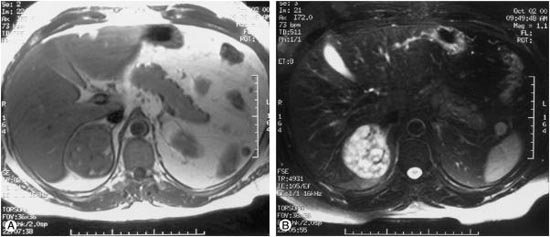

전산화단층촬영(CT)이나 자기공명영상(MRI)은 부신뿐만 아니라 주변 림프절 전이 또는 다른 장기로의 원격 전이 등을 평가할 수 있습니다. 양전자방출단층촬영(PET) 등도 보조적으로 부신과 림프절, 원격 전이 등을 평가하는데 사용되기도 합니다.

[ 부신 종양에 대한 자기공명영상 ]